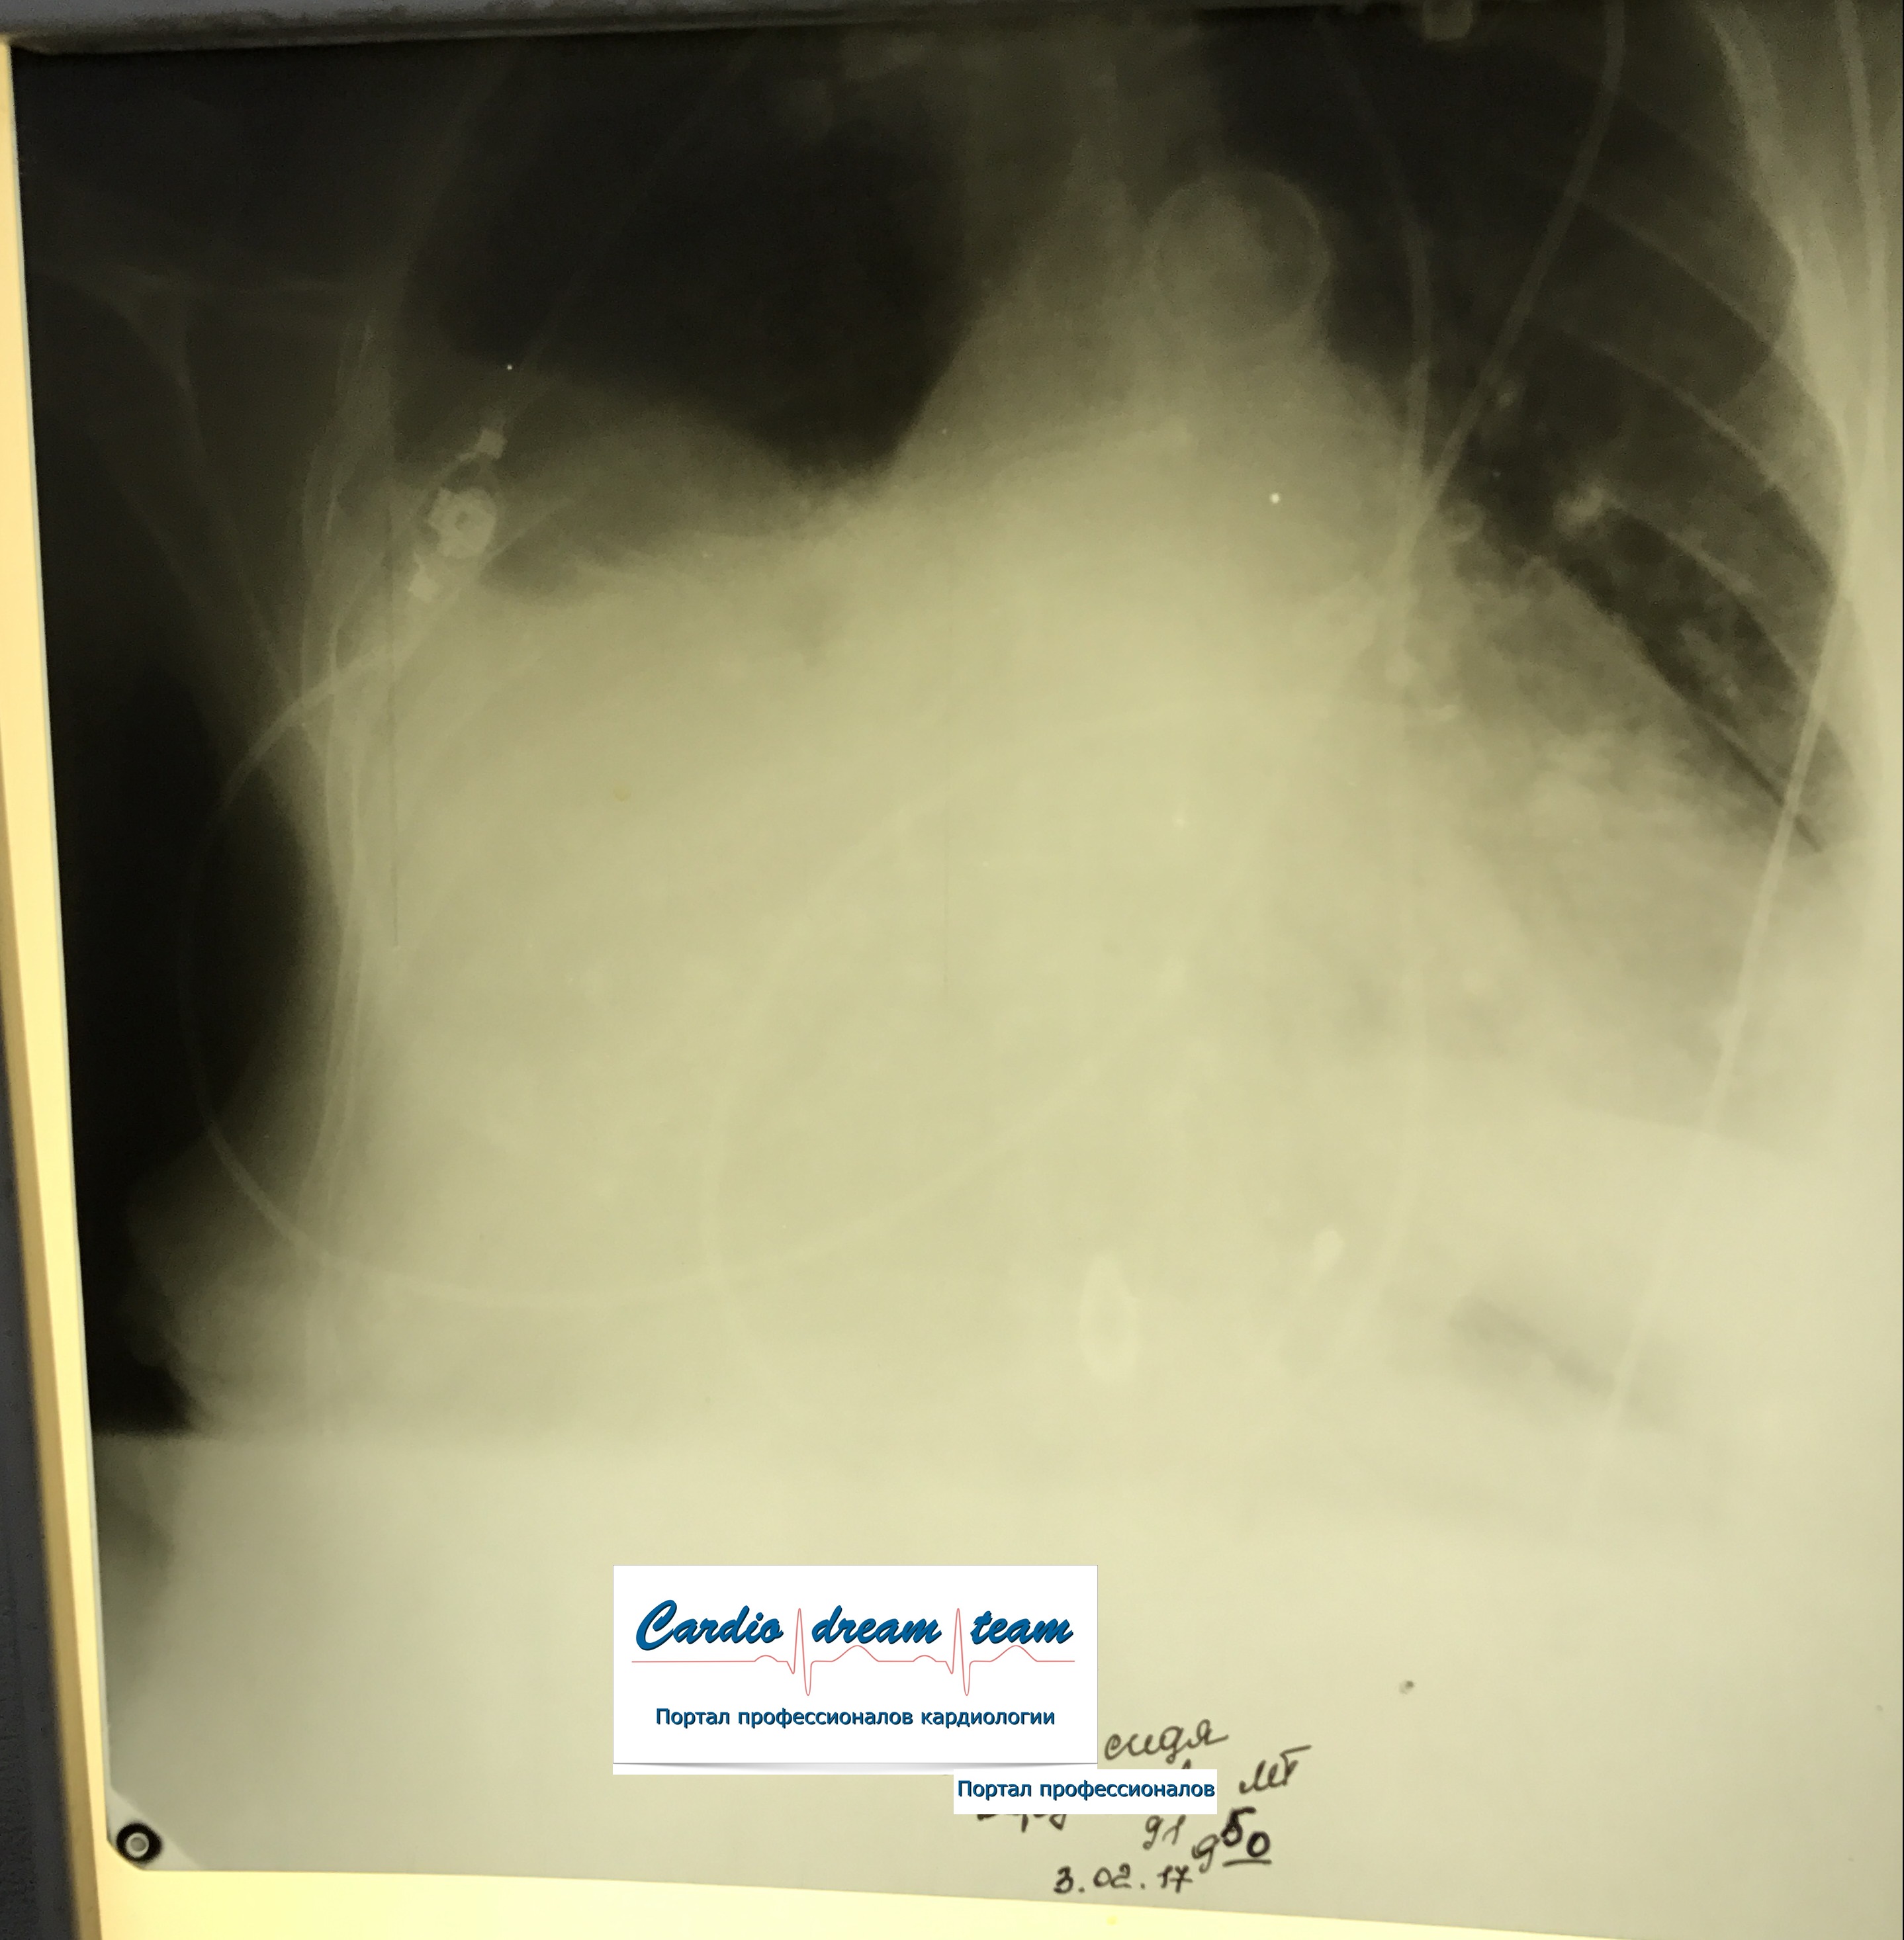

Левосторонний тотальный гемоторакс у женщины с раком правой молочной железы с метастазами в оба легких. Первый снимок при поступлении и после удаления 4 литров геморрагической жидкости.